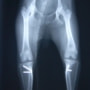

■ 症例22 ポメラニアン 1歳5か月 去勢雄

左後肢の挙上を主訴に来院した。整形学的検査、レントゲン検査より左右の膝蓋骨脱臼(左GradeⅡ〜Ⅲ、右Grade Ⅱ)を認めた。また、脛骨の前方引き出し試験の際に、引き出し兆候は認められないものの、疼痛が認められたため、前十字靭帯の損傷が疑われた。術中における、目視および関節内の操作によって、前十字靭帯の損傷や過伸展といった異常が認められなかったため、膝蓋骨脱臼の整復のみ実施した。手術手技は縫工筋及び内側広筋の解放、脛骨粗面の外側転位、滑車ブロック形造溝術、内外側関節包の縫縮を実施した。本症例は跛行もなく経過良好である。しかし、頸骨高平部の角度(TPA)が 右26.2°、左24.9°であり、解剖学的に前十字靭帯損傷のリスクが高いことから今後の経過に注意が必要である。